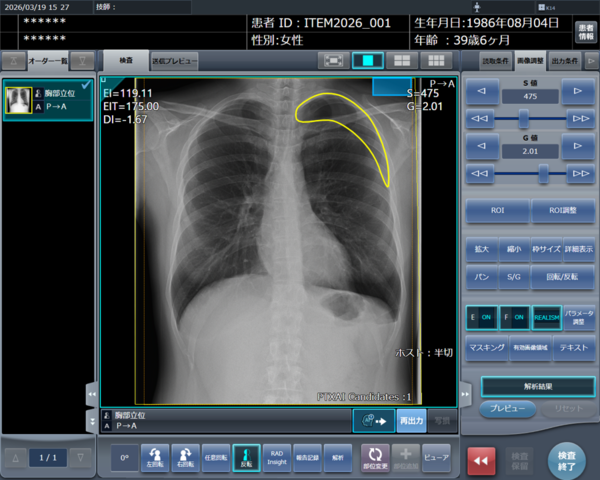

「CXR Finding-i 気胸検出タイプ」により解析された気胸の検出領域を表示

STAT画像所見報告の記録画面

「RADInsight」にデータを蓄積